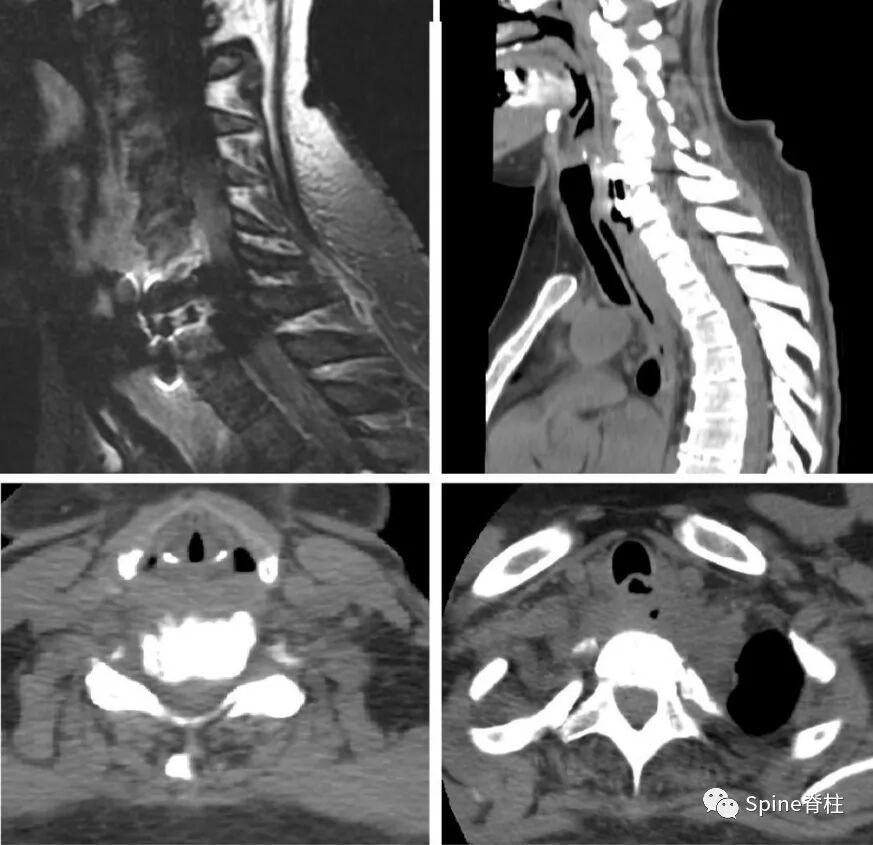

他们报告一位45岁女性,ACDF术后1年后发生食管憩室的病例。表现为发热、渐进性吞咽困难和颈部疼痛,有咽后感染的迹象。

他们进行了一期颈后路钉棒固定(C3-T1)和二期左侧颈前入路,钢板取出,食道后壁破裂处,胸骨舌骨肌皮瓣修复。目前患者临床症状稳定,无椎前感染症状,经皮内镜胃造口术可获得营养。对于残余憩室,胸外科医师正在评估进一步的手术(憩室切除术或憩室固定术)。

图示:术后咽后感染并延伸至纵隔

图示:食道内镜检查显示憩室与真正的食道腔有明显区别。憩室内有钢板和螺钉的迹象。

图示:术后6天食管无造影漏,但仍存在憩室。